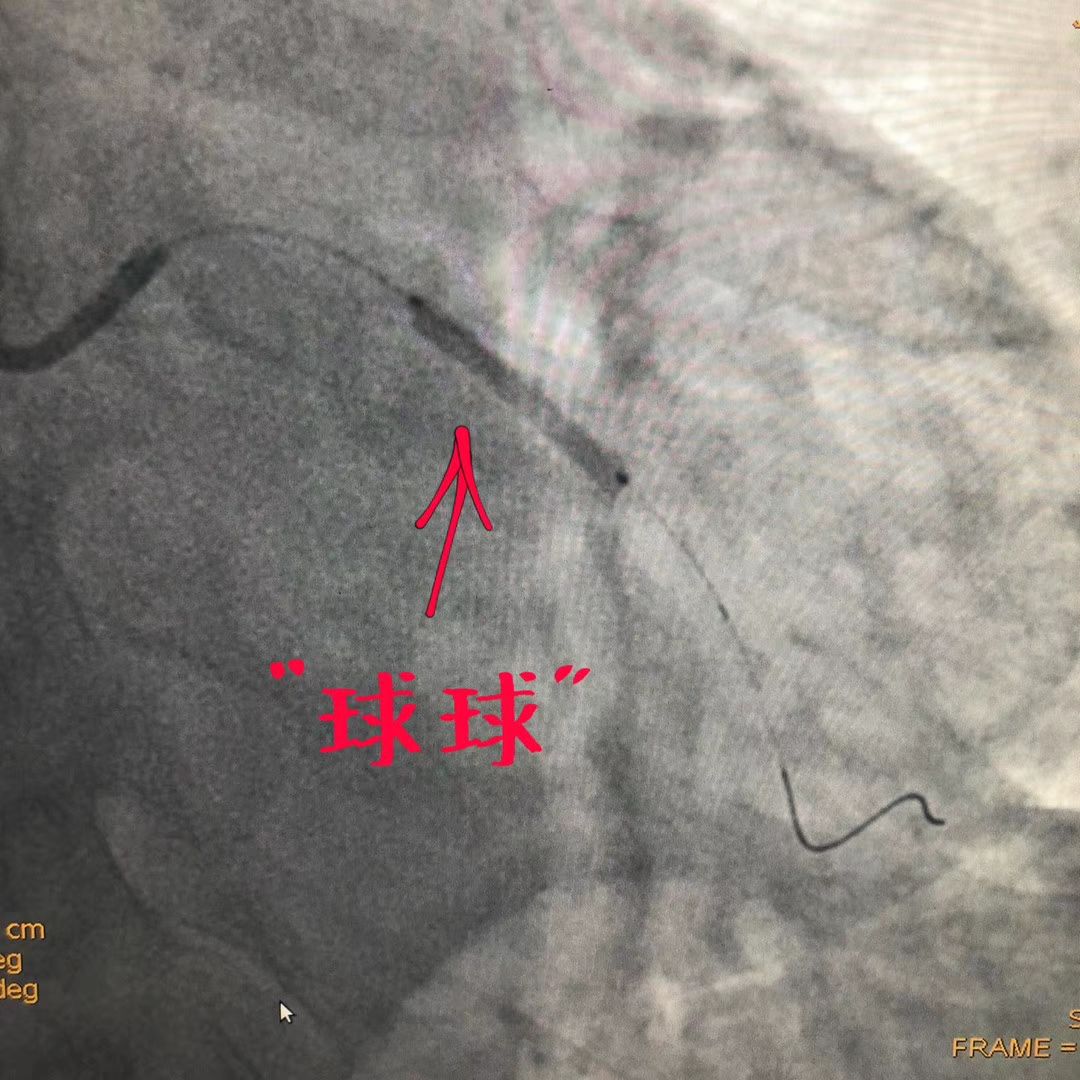

牡丹江市第二人民医院首例药物球囊治疗支架内再狭窄一例

图片尺寸750x562